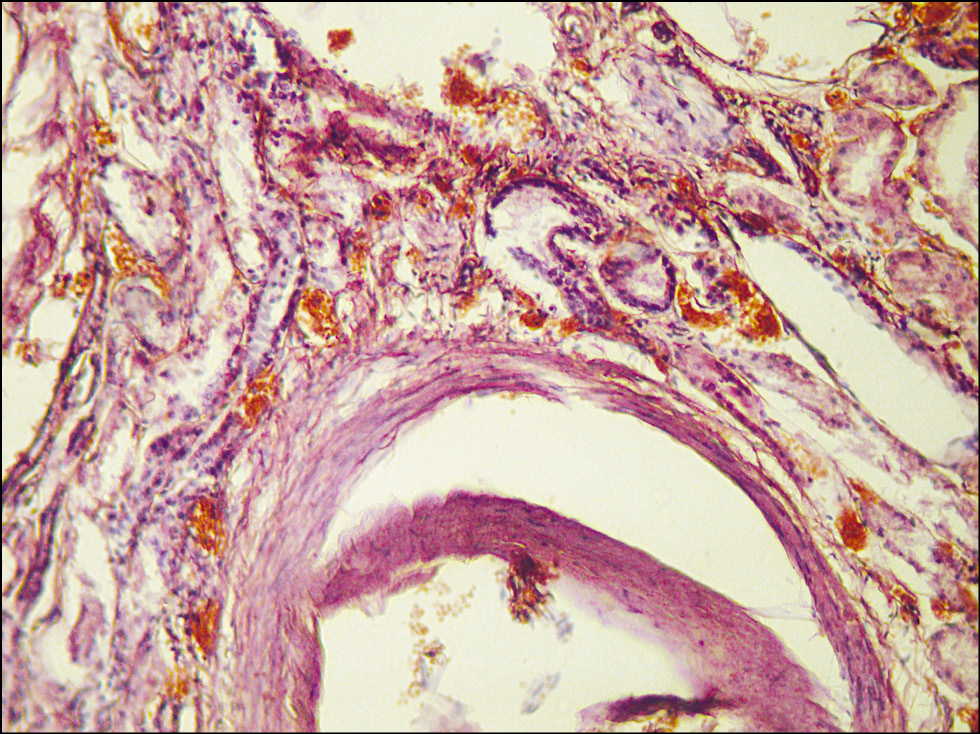

Микропрепарат почек: просветы сосудов интерстиция расширены, полнокровны; склероз части клубочков и сосудов стромы, отёк интерстиция; очаговый некронефроз; очаговая лимфоидная инфильтрация (рис. 8).

Рис. 8. Микропрепарат почек. Некронефроз. Окраска гематоксилином и эозином. Ув. 100. / Fig. 8. Kidney microslide. Necronephrosis. Staining with hematoxylin and eosin. Magnification 100